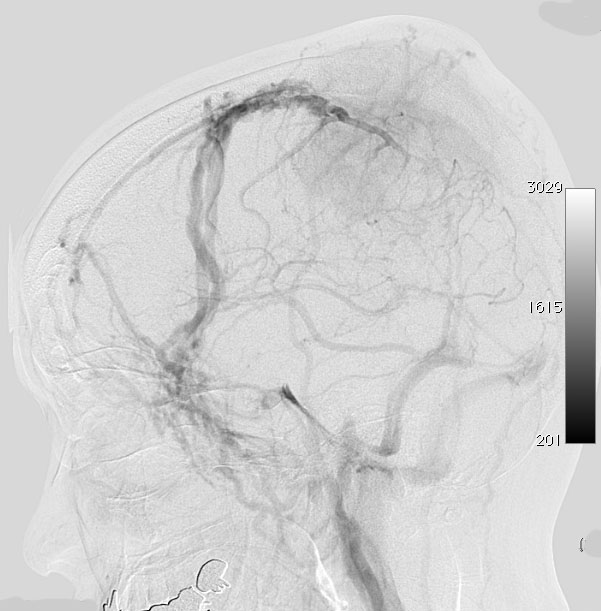

上矢状洞髄膜腫 superior sagittal sinus meningioma

上矢状洞を埋め尽くすように増大して,頭蓋骨浸潤が著しい髄膜腫ですが,ごく軽度の右足脱力以外に何の症状もありません。上矢状洞はゆっくり閉塞すれば,このような頭頂部から後頭部にわたる広範閉塞でも,静脈還流に障害がない場合が多いといえます。大脳の前半部の血流は前頭葉表面の皮質静脈から海綿静脈洞に側副路を形成しています。頭蓋内圧亢進所見もなく,これらはこの髄膜腫がゆっくり増大したということを示唆しています。

手術直後の画像です。全部いっぺんに摘出するのは無理なので,まず前から80%くらいの腫瘍を摘出しました。肥厚した骨はチタンプレートで置き換えてあります。後頭部の上矢状洞内と大脳鎌に少し残りましたが,この6ヶ月後に2回目の開頭術をして全摘出しました。結果的にこの例では,上矢状洞を冠状縫合のあたりから,静脈洞交会まで壁ごと全部摘出しましたが,脳浮腫も何も生じませんでした。腫瘍の両側にある皮質静脈 cortical veinsを損傷しないことが肝要です。

右の病理像は,頭蓋骨浸潤している部分 ですが,骨破壊は良性髄膜腫に特徴的な骨内浸潤像です。この骨浸潤像は悪性像とはいえません。MIB-1は高いところで8%、低いところで3%程度です。